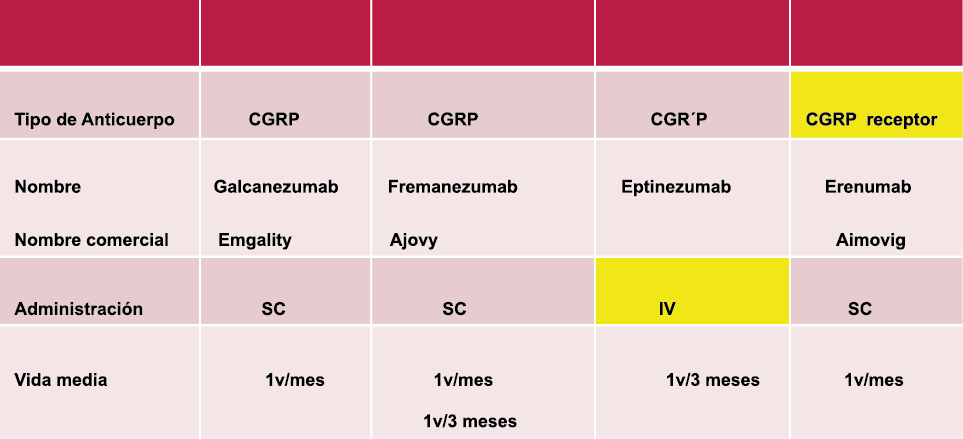

El CGRP es un potente vasodilatador que, cuando se administra a personas que padecen migrañas, se sabe que desencadena ataques(72). Se libera durante los ataques espontáneos(73) o provocados(74), que pueden inhibirse mediante el tratamiento con triptanos(75). Además de sus efectos vasculares, CGRP se ha convertido en un modulador clave de la función neuronal, que tiene efectos importantes en los sistemas de neurotransmisores como el sistema glutamatérgico(76). Sobre la base de los datos clínicos(77), se inició un esfuerzo para desarrollar antagonistas de los receptores de CGRP: los “gepantes”: telgacepant demostró una eficacia mejor que el placebo y comparable a los triptanos(78), como el primer antagonista oral del receptor de CGRP con excelente tolerabilidad a largo plazo(79) y también fue bien tolerado en pacientes que estaban siendo investigados por enfermedad arterial coronaria(80). Sin embargo, el desarrollo de telgacepant se detuvo cuando surgieron problemas con las enzimas hepáticas en un estudio preventivo, que resultó bastante positivo(81). Este efecto no se ha informado con rimagepant(82) Los ditanes, tienen como mecanismo el ser agonistas selectivos del receptor 5-hidroxitriptamina tipo 1F (5-HT1F) en la vía trigeminal, hasta ahora ha demostrado no tener efecto vasoconstrictor asociado. Lasmiditán ha sido hasta la fecha de elaboración de esta revisión la primera molécula aprobada por FDA. (Figura 35)

Los anticuerpos monoclonales contra el péptido CGRP y el receptor (numab y nezumabs) se han desarrollado para capitalizar los efectos antimigrañosos comprobados del bloqueo de los mecanismos CGRP como nuevos tratamientos preventivos. Los anticuerpos contra el péptido CGRP, al CGRP y del receptor CGRP (complejo CLR/RAMP1) han presentado datos positivos de ensayos controlados.(83) (Figura 36 y Tabla 3)

La comprensión de la biología de la migraña a través de una cuidadosa investigación de laboratorio ha llevado al desarrollo de las principales clases de tratamientos: triptanos, agonistas del receptor de serotonina 5-HT1B/1D; gepants, antagonistas del receptor del péptido relacionado con el gen de la calcitonina (CGRP); ditanes, agonistas del receptor 5-HT1F, CGRP anticuerpos monoclonales; moduladores de mGlu5, sin olvidar el efecto ya demostrado por parte de los bloqueantes de los canales de calcio (flunarizina) y de los neuromoduladores; bien se trate de topiramato (Inhibe la acción de la anhidrasa carbónica, bloquea los canales del sodio, aumenta las corrientes de cloro mediadas por GABA, activa las corrientes hiperpolarizantes del K+ e inhibe la activación de receptores a ácido glutámico tipo AMPA), valproato de sodio (Inhibe las enzimas de degradación del GABA y puede aumentar su síntesis, además de tener un papel inhibidor de la transmisión excitatoria de ciertos aminoácidos, entre ellos el glutámico y reducir el umbral de conductancia del calcio y el potasio) y de los antidepresivos de diversas clases como la amitriptilina (antidepresivo tricíclico que impide la recaptación y la inactivación de la noradrenalina y la serotonina en las terminaciones nerviosas) y venlafaxina (inhibe principalmente la recaptación de serotonina y en menor grado de noradrenalina, en la membrana presináptica neuronal, potenciando la neurotransmisión a nivel del sistema nervioso central). El propanolol tiene un efecto antagonista de los adrenoceptores β1 en las neuronas del núcleo VPM (postero medial ventral) del tálamo que responden a la entrada nociceptiva trigeminovascular. Se ha demostrado que el propanolol previene los cambios en el comportamiento y el flujo sanguíneo cerebral inducido por la depresión cortical propagada, además de bloquear los canales de sodio del cerebro(103), modulación del sistema catecolaminérgico central(104) probablemente a través de receptores β-adrenérgicos centrales e interacción cruzada con receptores de serotonina(105) (Figura 4).